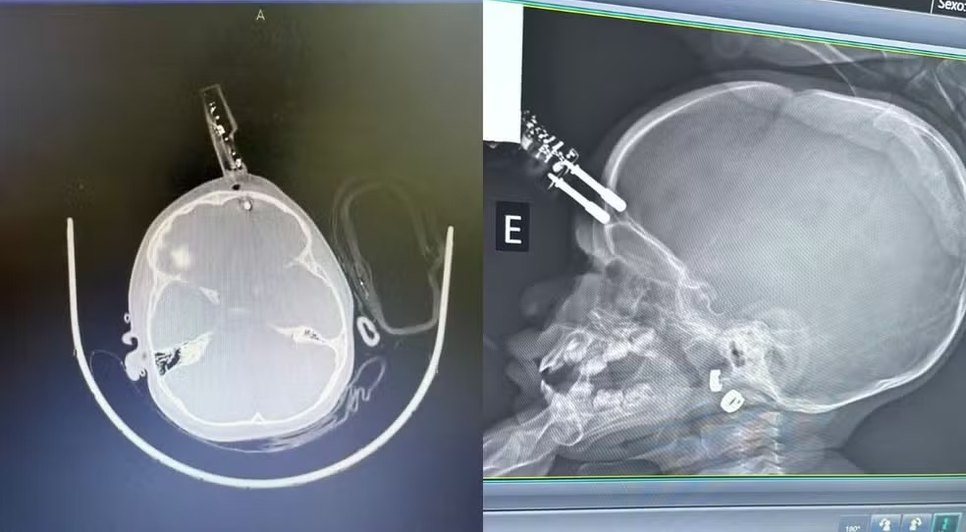

Uma menina de 1 ano precisou passar por uma cirurgia de emergência após cair da cama e ter um carregador de celular cravado na testa, em Divinópolis. Segundo o neurocirurgião responsável pelo atendimento, a criança segue internada, sem sinais de sequelas neurológicas até o momento.

O acidente ocorreu quando a mãe teria se ausentado por alguns instantes. A criança segurava o carregador ao cair, fazendo com que o objeto perfurasse a região frontal do crânio, próximo ao olho. Ela foi imediatamente levada ao bloco cirúrgico, onde o dispositivo foi retirado, a área limpa e reconstruída.

O médico alertou que o principal risco em casos assim é a lesão cerebral, já que o objeto atravessou o osso e atingiu o cérebro, podendo causar hemorragia. A perfuração também aumenta o risco de infecção, como meningite. A criança recebe antibiótico profilático e seguirá em acompanhamento neurológico devido à possibilidade de complicações futuras.